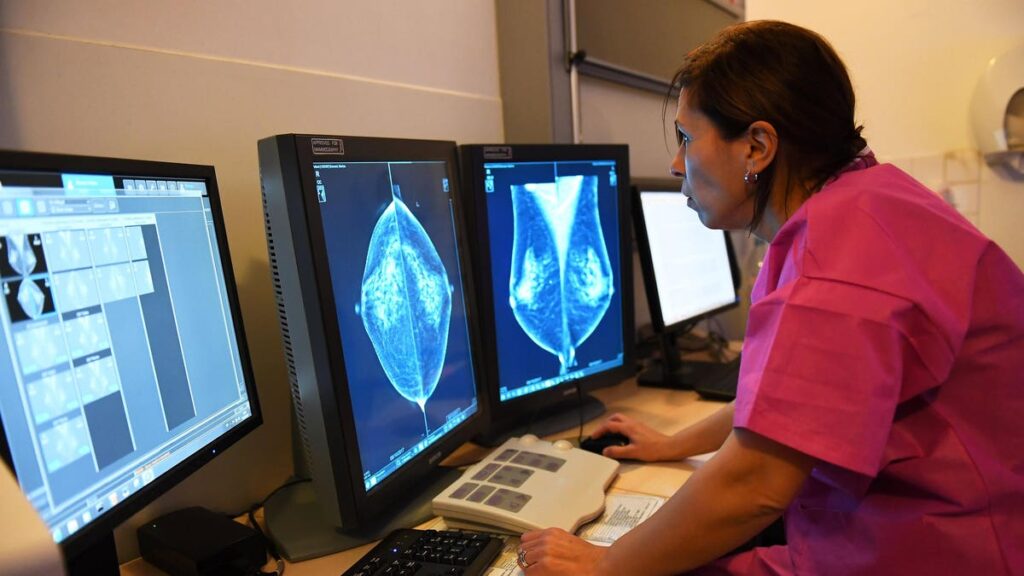

Doctor Rim Villard looks at the results of a mammography, on October 9, 2017 at the Paoli-Calmette … [+]